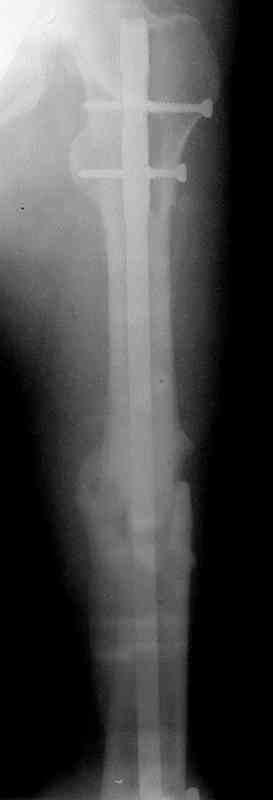

по его наружной поверхности послеоперационный рубец - рана зажила первичным натяжением. При измерении длины бедер обнаружено укорочение левого бедра на 4,5 см. На рентгенограммах этого бедра: ось конечности правильная, отмечается захождение основных костных фрагментов по длине, проксимальный конец штифта выступает слишком медиально и высоко относительно большого вертела, периостальная мозоль незначительна.22.12 - через 6 месяцев после операции, произведенной в ЦРБ, нами по поводу замедленно консолидирующего перелома левой бедренной кости с ее абсолютным укорочением под наркозом произведена операция: удаление штифта, закрытый блокирующий интрамедуллярный остеосинтез перелома левого бедра штифтом без рассверливания (UFN) длиной 40 см, диаметром 10 мм с блокированием только проксимальных отверстий (динамический остеосинтез). Наложен аппарат Илизарова на 4 полукольцах с целью удлинения укороченного бедра. Послеоперационное течение без особенностей. Ежедневно осуществляли дистракцию отломков на 1 мм. Через 3 недели после операции больной выпи-сан на амбулаторное лечение с продолжением дистракции отломков. В течение 1,5

месяцев дистракции укорочение левого бедра удалось полностью устранить. 22.02.00, т.е. через 2 месяца после повторного остеосинтеза, больному произведено дистальное блокирование штифта двумя винтами и демонтирован аппарат Илизарова. В течение 2 недель после операции больной ходил с помощью костылей, потом 2 недели с тростью. Опороспособность и функция оперированной конечности полностью восстановились через 4 недели после операции.

Фиксаторы удалены через 12 месяцев после операции, выполненной по поводу замедленной консолидации перелома бедра с его укорочением.